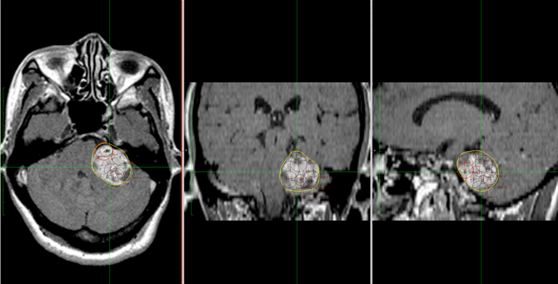

Hình 1. Hình ảnh chi tiết kế hoạch xạ phẫu bằng dao gamma quay ở ba mặt phẳng tọa độ của một bệnh nhân nữ, 64 tuổi, bị u dây thần kinh số VIII bên trái, tại Trung tâm Y học hạt nhân và Ung bướu-Bệnh viện Bạch Mai .